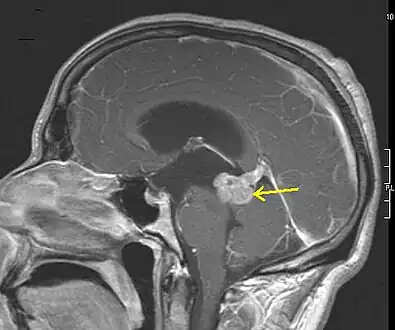

- Low grade astrocytoma of the midbrain (lamina tecti), sagittal T1-weighted magnetic resonance imaging after contrast medium administration: The tumor is marked with an arrow. The CSF spaces in front of the tumor are expanded due to compression-induced hydrocephalus internus.